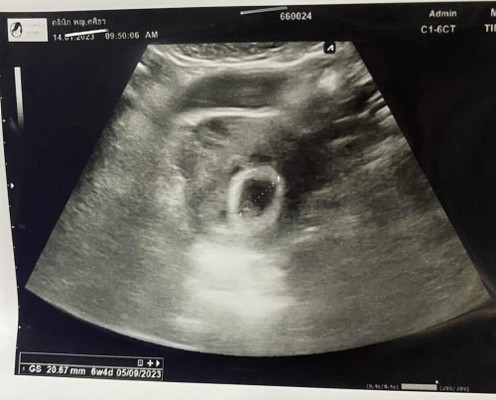

ไม่น่าจะเป็นท้องลมนะคะ ถ้าเป็นท้องลมส่วนมาก จะซาวไม่เจอถุงไข่แดงค่ะ ท้องแรกเคยท้องลม ซาวไม่เจอถุงไข่แดงค่ะ ท้องนี้ท้อง 2 ได้ 9 w แล้วซาวครั้งแรก ตอน 5 w ก็เจอถุงไข่แดงนะคะ

เหมือนกันเลยค่ะ เจอแต่ถุงไข่แดง ยังไม่เจอตัวอ่อน หมอนัดอีก2อาทิต กังวลมากๆเลยค่ะ บางทีไข่อาจจะตกช้าก็ได้นะคะ ลุ้นๆไปด้วยกันคะ

อายุครรภ์ยังน้อยต้องซาวด์กับทางช่องคลอดถึงจะเห็นชัดนะคะแม่ ของแม่ซาวด์ทางช่องคลอดไหมคะ

ซาวด์หน้าท้องค่ะแม่ หมอนัดซาวด์อีกทีวันที่ 11 กพ ค่ะ ก้อจะได้ประมาณ 10 วีคค่ะ ช่วยลุ้นหน่อยนะคะคุณแม่

ไม่น่าจะท้องลมนะคะ เพราะจากประสบการณ์ท้องลม2ครั้ง ซาวด์ไม่เจอถุงไข่เเดงเลยค่ะ